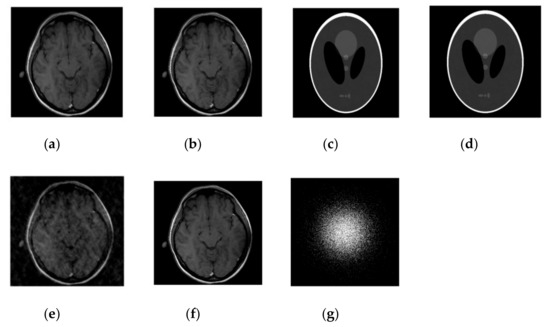

Graphs in Figure 5a,b are shown for a noisy case with 4 fold Cartesian under sampling for reconstruction of a phantom image.

Figure 5.

Algorithms performance in noisy case with cartesian sampling. (a) PSNR vs iterations with comparison to DLMRI for a phantom image (b) HFEN vs iterations with comparison to DLMRI for a phantom image (c) Cartesian sampling scheme with 4 fold. (d) Recovered image.

Performance comparison of SiFo vs DLMRI for noisy brain images for radial sampling are shown in Figure 6 and Table 3.

Figure 6.

Algorithms performance of SiFo vs DLMRI in a noisy case with radial sampling mask. (a) PSNR vs iterations for a phantom image; (b) HFEN vs iterations for a phantom image; (c) Recovered MR image of a brain by SiFo; (d) Recovered MR image of a brain by DLMRI; (e) Radial sampling mask in k-space with a 6.1 fold undersampling.